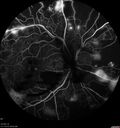

49 year old man with vision loss in the right eye for 2 weeks. VA 20/40 OD, 20/63 OS. DM x 15 years and HTN.